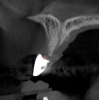

Tomographic images revealed a large tridimensional defect, with vertical and horizontal loss of bone extending to the apical third of teeth Nos. 6 and 8. Additionally, a buccal bone dehiscence was evident on tooth No. 5, and thin labial plates secondary to the orthodontic movement were present in several areas (Figure 3 and Figure 4).

Fig 3. Tomographic images revealed a tridimensional defect extending to the apical third of teeth Nos. 6 and 8, a buccal bone dehiscence on tooth No. 5, and associated thin labial plates.

Figure 3